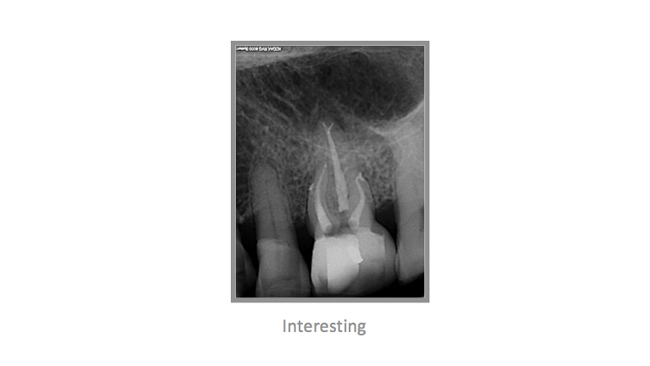

• A few Teeth Treated by Dr. Katsarsky

• A few Cases Treated by Dr. Katsarsky